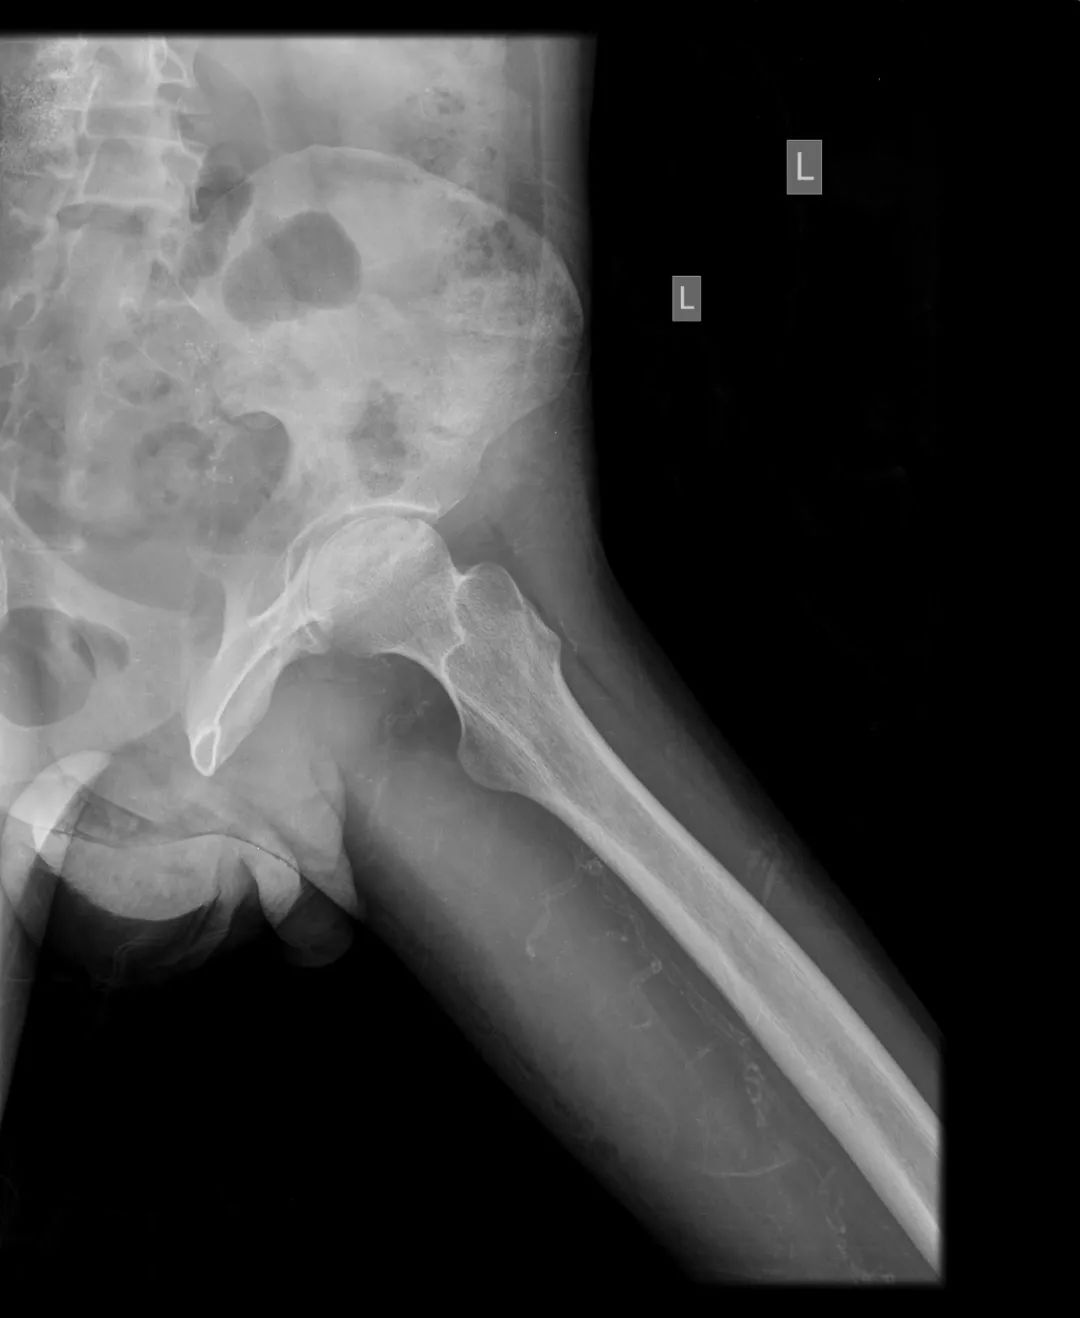

CASE M25 年轻男性,已知有类固醇治疗狼疮性肾炎史。伴有双侧髋关节疼痛和运动困难的抱怨。

不规则的透光区,代表软骨下囊变,与边缘硬化在两个股骨头。双股骨头呈线性软骨下骨折/断裂,伴有轻度塌陷/扁平。这些发现代表了双侧股骨头缺血性坏死。